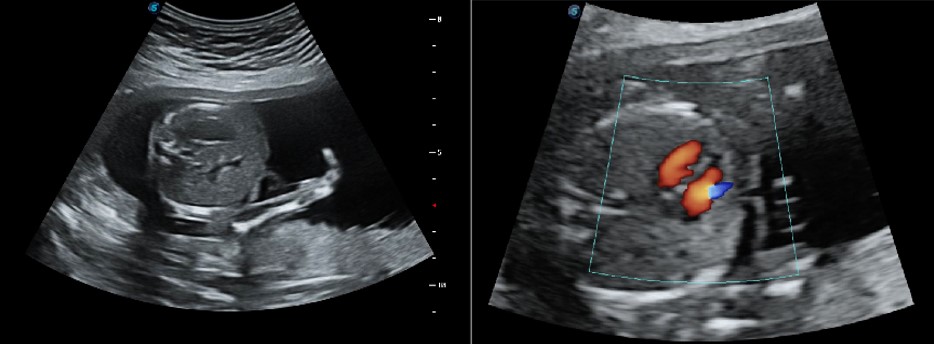

S-Live/Hdlive/5D

S-Live cho phép hiển thị chi tiết các đặc điểm giải phẫu tinh vi, từ đó cho phép chẩn đoán trực quan với hình ảnh 3D thời gian thực và giao tiếp với bệnh nhân phong phú hơn.

Tầng chậu 4D

Siêu âm tầng sinh môn 4D qua tử cung có thể cung cấp những giá trị lâm sàng hữu ích trong việc đánh giá tác động của cuộc sinh qua ngả âm đạo lên ngăn trước của nữ giới, đánh giá xem các cơ quan vùng chậu có bị sa hay không và mức độ, xác định chính xác cơ vùng chậu có bị rách hay không.